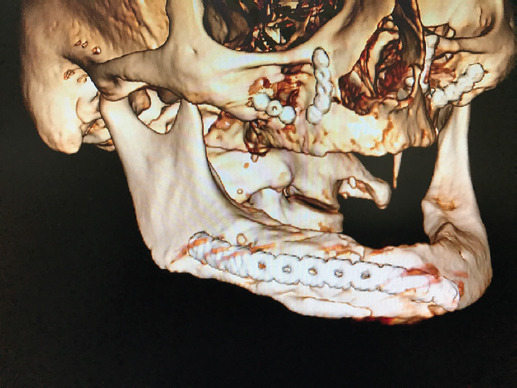

Se utilizó acceso extraoral en los pacientes tratados con placa universal de fracturas (tornillos 2.4) por la precisión en el amoldado de la placa y la simplificación de la fractura mediante una pequeña placa y tornillos 2.0 en el borde basal (para reducción anatómica de la fractura). En los pacientes tratados con sistemas bloqueados 2.0 sin injerto, las fracturas mandibulares fueron tratadas por vía intraoral (Fig. 4) por las libertades del amoldado de este tipo de placas; las subcondíleas fueron tratadas por acceso retromandibular (Fig. 5) para osteosíntesis con placas y tornillos. En caso de utilizar injerto óseo, aun con placas cerrojadas, el acceso extraoral (Fig. 6) se decidió con idea de disminuir las posibilidades de contaminación del injerto.

Figura 6 Acceso extraoral para tratar una fractura bilateral de cuerpo mandibular. Ambas fracturas simplificadas con placas y tornillos cortos en el borde basal previo a la osteosíntesis con placa bloqueada y aplicación de injerto óseo.

Respecto al acceso quirúrgico, se debe considerar la reducción de la fractura, situación que puede presentar dificultades según su localización y trazo, la presencia de fracturas bilaterales (cuerpo), el desplazamiento debido a la tracción muscular local y la carencia de órganos dentarios para lograr restituir la oclusión dentaria, así como la necesidad de aplicar injerto óseo. En casos de atrofia es de enorme utilidad lograr la reducción anatómica mediante la aplicación de placas pequeñas y tornillos cortos transoperatoriamente (6 mm de longitud y 2 mm de diámetro) en el borde basal para simplificar la fractura, a través de un acceso extraoral transcervical (alineado en los pliegues del cuello), más caudal, en comparación con el tradicional submandibular, y realizando la disección inicial por debajo del platisma. De esta forma se tienen menores posibilidades de afección a las ramas caudales del nervio facial; además, es un plano de disección identificable sin contratiempo y de baja morbilidad, con ventajas estéticas al disimularse entre los pliegues del cuello, y disminuye notoriamente la fibrosis.

Ante la necesidad de aplicación de injerto óseo para mejorar la calidad del proceso de consolidación debe considerarse el uso de TC preoperatoria para evaluar la densidad ósea mandibular en los extremos de la fractura. Debe buscarse intencionalmente como parte de la planificación preoperatoria la presencia de hueso esponjoso en los extremos de la fractura4,8,9,10. Otro aspecto a considerar, es la posibilidad de que la disección de la mandíbula para la aplicación de la placa se haga sub- o supraperióstica. Quienes argumentan la ventaja de colocar las placas sobre el periostio señalan que no se disminuye más el aporte vascular mandibular y, por lo tanto, se presentarán con menor frecuencia trastornos de consolidación. La aplicación de material de osteosíntesis subperióstico, respetando las inserciones del periostio y obviamente las musculares sobre la superficie lingual mandibular, es suficiente para no alterar la vascularidad y como consecuencia el proceso de consolidación por la desperiostización de la superficie vestibular mandibular. Sin embargo, no se debe menospreciar la estabilidad mecánica que se obtiene al realizar osteosíntesis mandibular, como un efecto benéfico para mejorar el proceso de consolidación. Se ha publicado la posibilidad de aplicar la osteosíntesis en el borde basal mandibular6,9 con la finalidad de que tenga menor interferencia con la adaptación protésica, mejor cubierta de los tejidos blandos sobre la placa y menores posibilidades de dehiscencia del acceso quirúrgico, en caso de acceso intraoral.